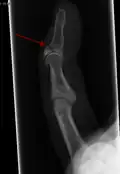

Le diagnostic est généralement basé sur les symptômes et confirmé par des radiographies[1]. La lésion peut être accompagnée d'un œdème et d'une ecchymose[3].

- Radiographie montrant une fracture à l'insertion du tendon extenseur